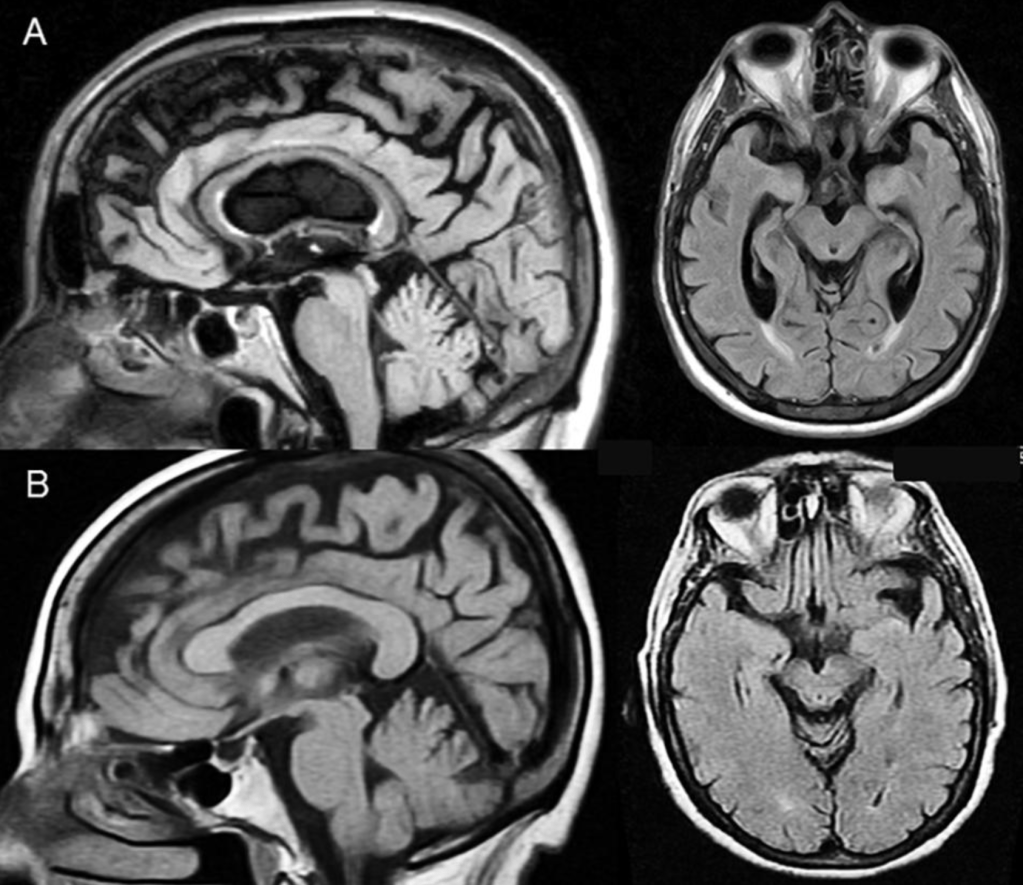

In aphasias associated with cerebrovascular disease, echolalia may arise not only as a consequence of a frontal “release” lesion affecting the perisylvian circuit, but also secondarily to deep posterior injuries that disrupt the broader language network. In the case described by Abusrair and AlSaeed, diffusion imaging shows an infarct involving the left inferior parietal lobule, parieto-occipital regions, internal capsule, and the splenium of the corpus callosum—that is, a neuroanatomically critical site where association and projection fibers converge, connecting temporoparietal areas with other regions of the hemisphere and with the contralateral side.

This pattern of injury does not completely destroy the perisylvian machinery for repetition, but it does alter the integration between auditory perception, semantic processing, motor control of speech, and interhemispheric networks. The resulting clinical picture is one in which repetition remains relatively preserved while spontaneous language and effective communication are impaired.

In this context, echolalia can be understood as an echo bouncing within a partially disconnected system: the words of others still find their way to articulation, even though the bidirectional exchange required for coherent discourse has been lost.